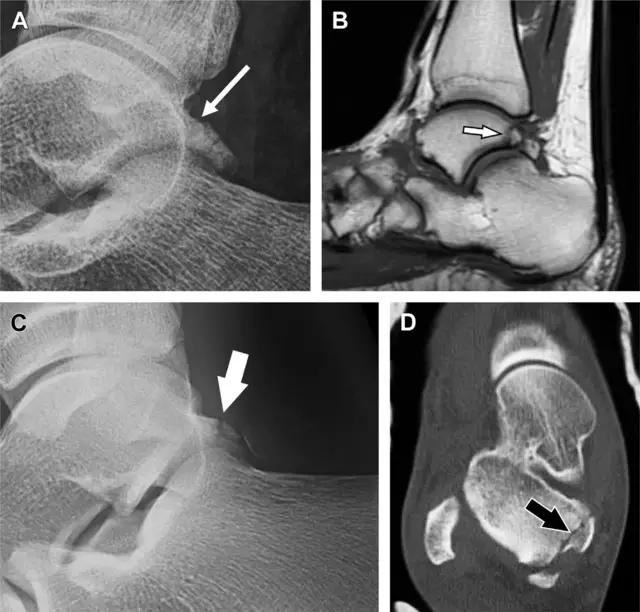

19 距骨后突骨折

距骨后突有内侧结节和外侧结节,距骨后突内侧结节撕脱性骨折常发生在背屈内旋的*力暴**作用下。严重跖屈时,胫骨后缘和跟骨挤压距骨后突外侧结节呈楔形,易发生粉碎性骨折。这些骨折细微且需与三角骨鉴别。侧位片观察距骨后突骨折最佳,常规拍片很难发现,当高度怀疑这种骨折又没法做 CT 时,建议加做多个角度的外旋斜位片(图 5)。

图 5 距骨后突骨折。侧位片(A)和 MRI 矢状位 T1 加权像(B)均示后外侧突的简单骨折(箭头),再次阅片时才发现 X 线片上的骨折;侧位片(C)和 CT 横断面图像示后内侧突的粉碎型骨折(箭头)

20 跟骨前突骨折

呈 Y 形的分歧韧带附着于跟骨前突上,是维持踝关节跖屈和背屈稳定性的重要结构。跟骨前突骨折常发生于足跖屈内旋、分歧韧带被牵拉时,或者足背屈外旋、骰骨和距骨挤压前突时。而这些骨折在初次 X 线检查时常常被漏诊掉。踝部侧位片诊断这些骨折最佳,准确诊断的关键点在于,必须仔细查看是否存在骨皮质中断(图 6)。如果侧位片可疑,建议加做斜位片协助诊断。

图 6 跟骨前突骨折。A 侧位片示跟骨前突骨折(箭头),与舟骨的重叠使骨折显示模糊;B 另一位患者的侧位片示内翻损伤所致的骨折(箭头),这种损伤机制引起小块的骨折